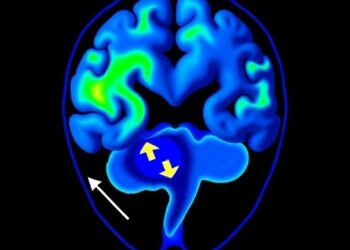

In a groundbreaking advancement at the crossroads of neuroscience and artificial intelligence, researchers have unveiled an innovative approach to understanding ...